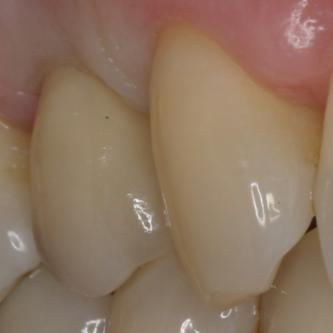

Exemple 3: Un implant à la place d'une incisive latérale supérieure droite. Sur cette image on voit le moignon en titane qui est vissé sur l'implant.

Exemple 3: Puis sur ce moignon, la couronne en céramique est scellée.

Exemple3: La couronne en place.